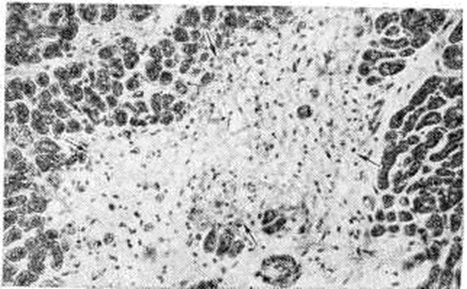

Экссудативный компонент представлен жидкой частью крови и её форменными элементами в различных соотношениях. Преобладание серозного экссудата с небольшим количеством лейкоцитов приводит к развитию острого серозного Миокардит, встречающегося при токсико-инфекционных поражениях миокарда различной этиологии. При этом пучки мышечных волокон раздвинуты серозным экссудатом, содержащим небольшое количество клеток крови, чаще всего — сегментоядерные лейкоциты. Наблюдаются случаи экссудативного Миокардит с преобладанием эозинофилов в экссудате и инфильтратах. Эозинофильный Миокардит нередко является частью синдрома Леффлера и сопровождается эозинофилией и эозинофильной инфильтрацией органов — лёгких, селезёнки и другие (смотри полный свод знаний Леффлера синдром). К клеткам экссудата иногда присоединяются клетки лимфогистиоцитарного инфильтрата из межуточной ткани сердца. Клетки инфильтрата частично трансформируются в клетки плазмоцитарного ряда, и иногда инфильтрат состоит (в основном) из плазматических клеток (смотри полный свод знаний); в этих случаях можно говорить о плазмоцитарном Миокардит (рисунок 6). При длительном течении Миокардит нарастают процессы фиброплазии за счёт размножения фибробластов межуточной ткани сердца и фиброцитарного превращения гистиоцитов. В результате очаг воспаления замещается рубцовой тканью и развивается миокардитический кардиосклероз.

Обычно при Миокардит выявляются изменения внутримиокардиальных кровеносных сосудов по типу гиперергического васкулита. Обнаруживаются все стадии васкулита — от фибриноидного некроза до склероза сосудистой стенки с частичной или полной облитерацией просвета сосуда (рисунок 7). Последовательность, при которой пролиферативные процессы следуют за начальными экссудативными, вовсе не является обязательной схемой. Лимфогистиоцитарная инфильтрация может развиваться с первых моментов воспалительной реакции, которая течёт по типу острого пролиферативного воспаления. Как видно из изложенного, при неспецифическом Миокардит отсутствует какая-либо специфика, позволяющая судить об его этиологии. Неспецифическими являются многие Миокардит при инфекционные заболеваниях, тонзиллогенный, лекарственный, поствакцинальный Миокардит, а также Миокардит при миастении, миокардит Абрамова—Фидлера.